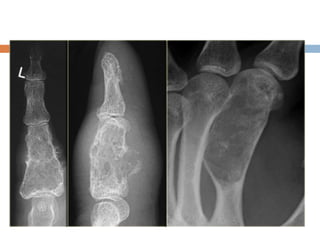

Chondroma

 Benign lesions of hyaling cartilage

 Common

 Affects all age groups

 Any bone can be involved but mainly affects

phalanges of the hands and feet

 Usually asymptomatic and discovered

incidentally or after a pathologic fracture

 Enchondromas: arise in the medullary cavity

Diagnosis

 Radiography

 Benign appearing tumors

 Translucent

 Intralesional calcification– irregular

(stippled/punctate/popcorn)

 Small bones of hand hands and feet–

considerable erosion and expansion of the

overlying cortex

 Long bones– deep endosteal erosion (>2/3 of

the thickness of cortex) indicates a

chondrosarcoma

 Associated soft tissue mass– indicates